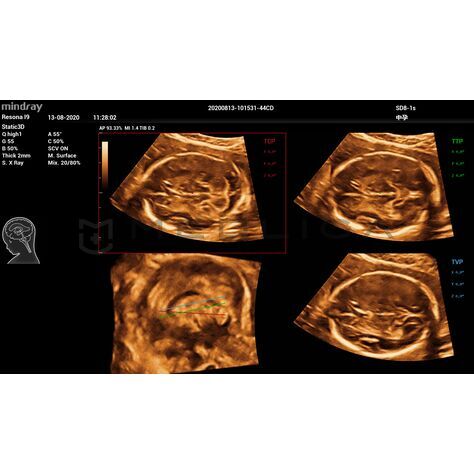

При нажатии на трехмерное изображение мозга плода незамедлительно будут получены

стандартные сканируемые плоскости ЦНС:

- MSP — интеллектуальная медиальная сагиттальная плоскость

- TCP — трансцеребральная плоскость

- TTP — трансталамическая плоскость

- TVP — трансвентрикулярная плоскость